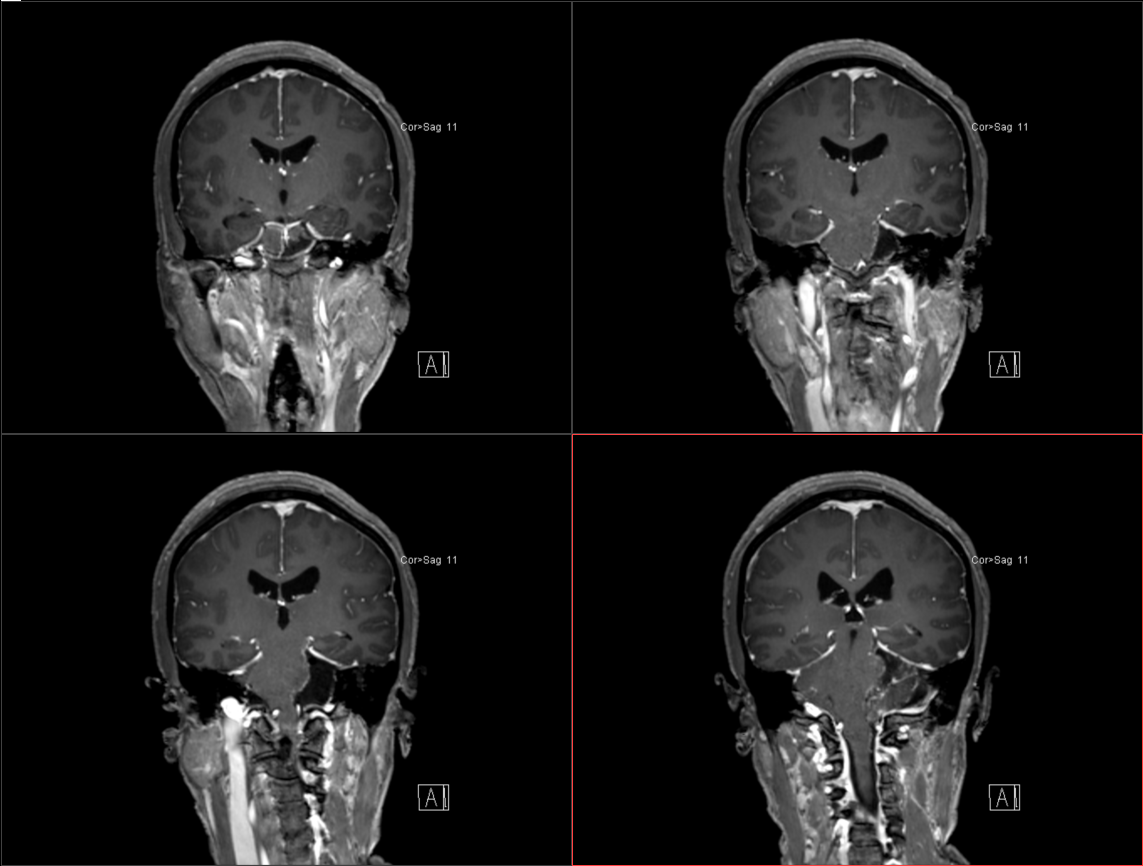

患者于入院前半年无明显诱因出现头痛、头晕,较剧烈,可耐受,无恶心、呕吐,无意识丧失,口服“止痛药(具体药名、剂量不详)”后症状稍缓解,入院前1周上述症状较前加重,患者前往当地医院就诊,行头颅MR示:1.左侧桥小脑角区占位,结合平扫及增强,现多考虑:皮样或表皮样囊肿。2。幕上梗阻性脑积水、脑室轻度积水。3.右侧上颌炎。现转至我院就诊。

术前影像: